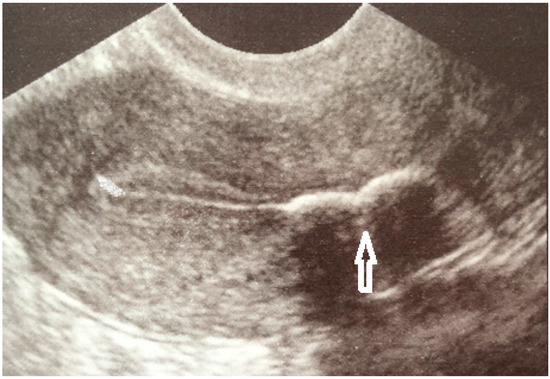

移植 内膜钙化灶